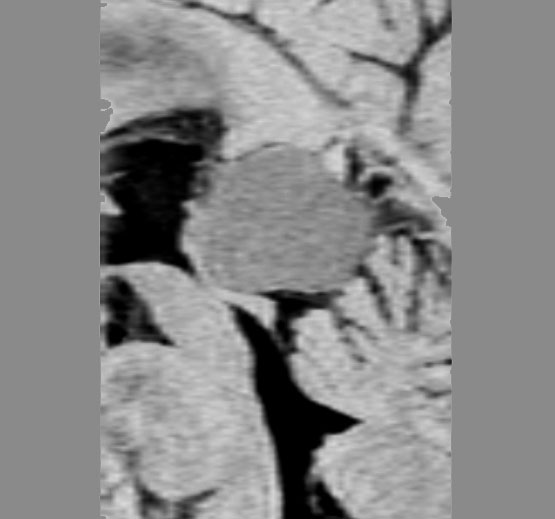

比較的急速に視力低下して手術摘出した例

右目が暗いという症状で発症して,眼科では視神経乳頭腫脹とわずかな視野欠損だけで発症した患者さんです。3年間観察されましたが,その間には眼底所見も視力 Vd 1.2 も変化がなかったとの眼科からの報告です。そのすぐ後で患者さん本人は,右目が暗くなる回数が増え、視野狭窄があり軽い眼球突出,まわりがぼやけてますが中心は1.0見える状態との訴えで相談を受けました。主治医の先生の方針では経過観察ということで,まだ視力も良いので私もそうした方がよいと同意したのですが,その後半年くらいで視力が手動弁まで低下してしまいました。眼球運動と右眼球を温存するために腫瘍を摘出しました。

左側は,摘出標本の輪切りの写真です。この部位は腫瘍の発生した部位ではありません。一番外側にみえるのは視神経鞘 optic sheathという膜です。その内側が髄膜腫で,その内側が視神経です。すなわち髄膜腫は,視神経鞘と視神経の間のくも膜下腔を,這うように伝わって増殖伸展しています。このくも膜下腔には視神経への栄養動脈や網膜動脈も入っているので,この腫瘍だけを視神経や細動脈を傷つけずに摘出することはできないのです。